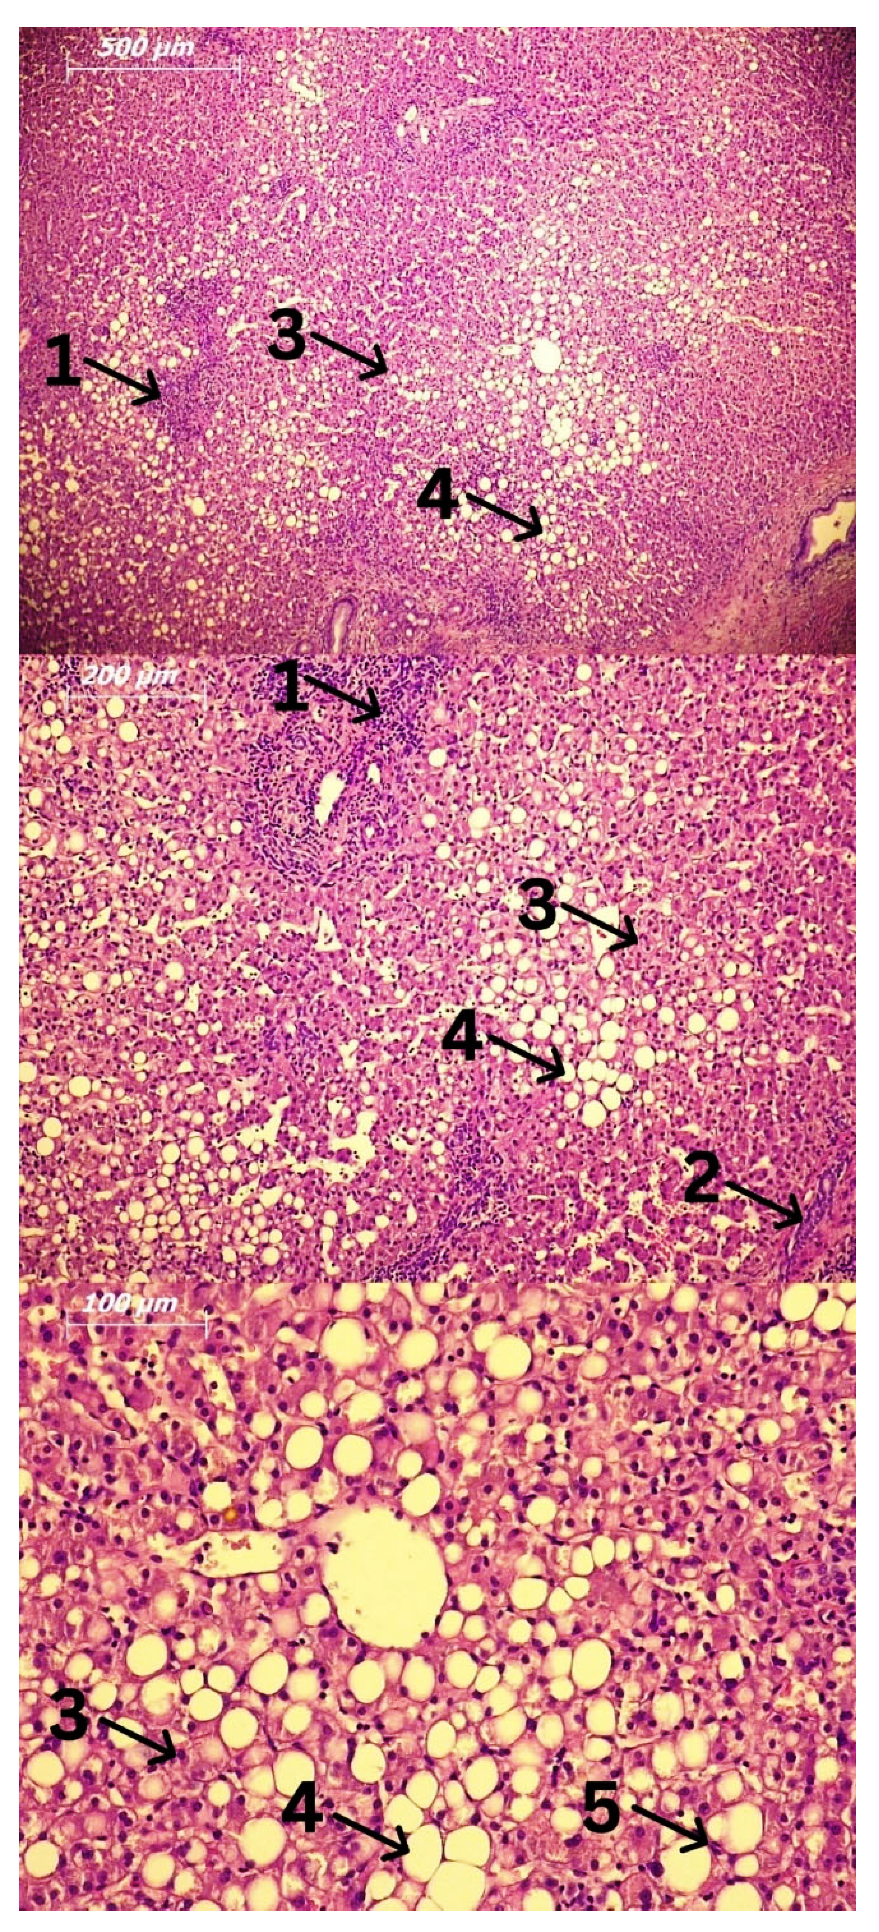

3. Cells Involved in the Pathogenesis of Alcoholic Liver Disease (ALD) and Alcoholic Steatohepatitis (ASH)

3.4. Hepatocytes and Hepatic Stellate Cells